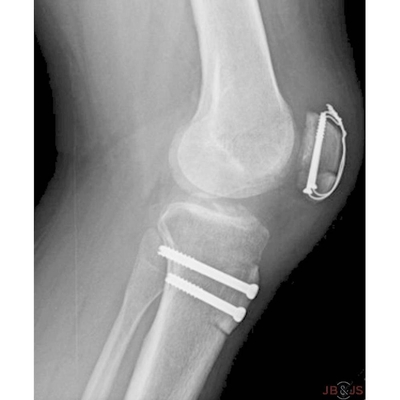

Click on an image below to view more info.